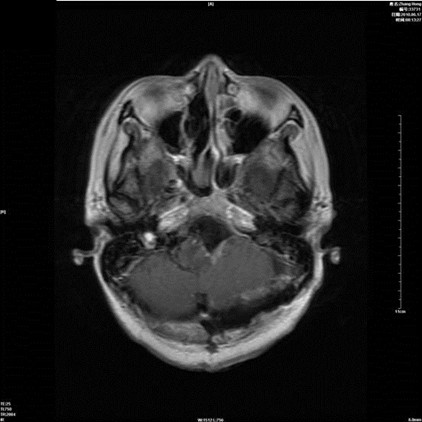

病例一:张**。女性,52岁。查体发现枕骨大孔区占位入院。临床诊断:枕骨大孔区腹侧脑膜瘤。术式:远外侧入路。术后病理脑膜瘤。

术前